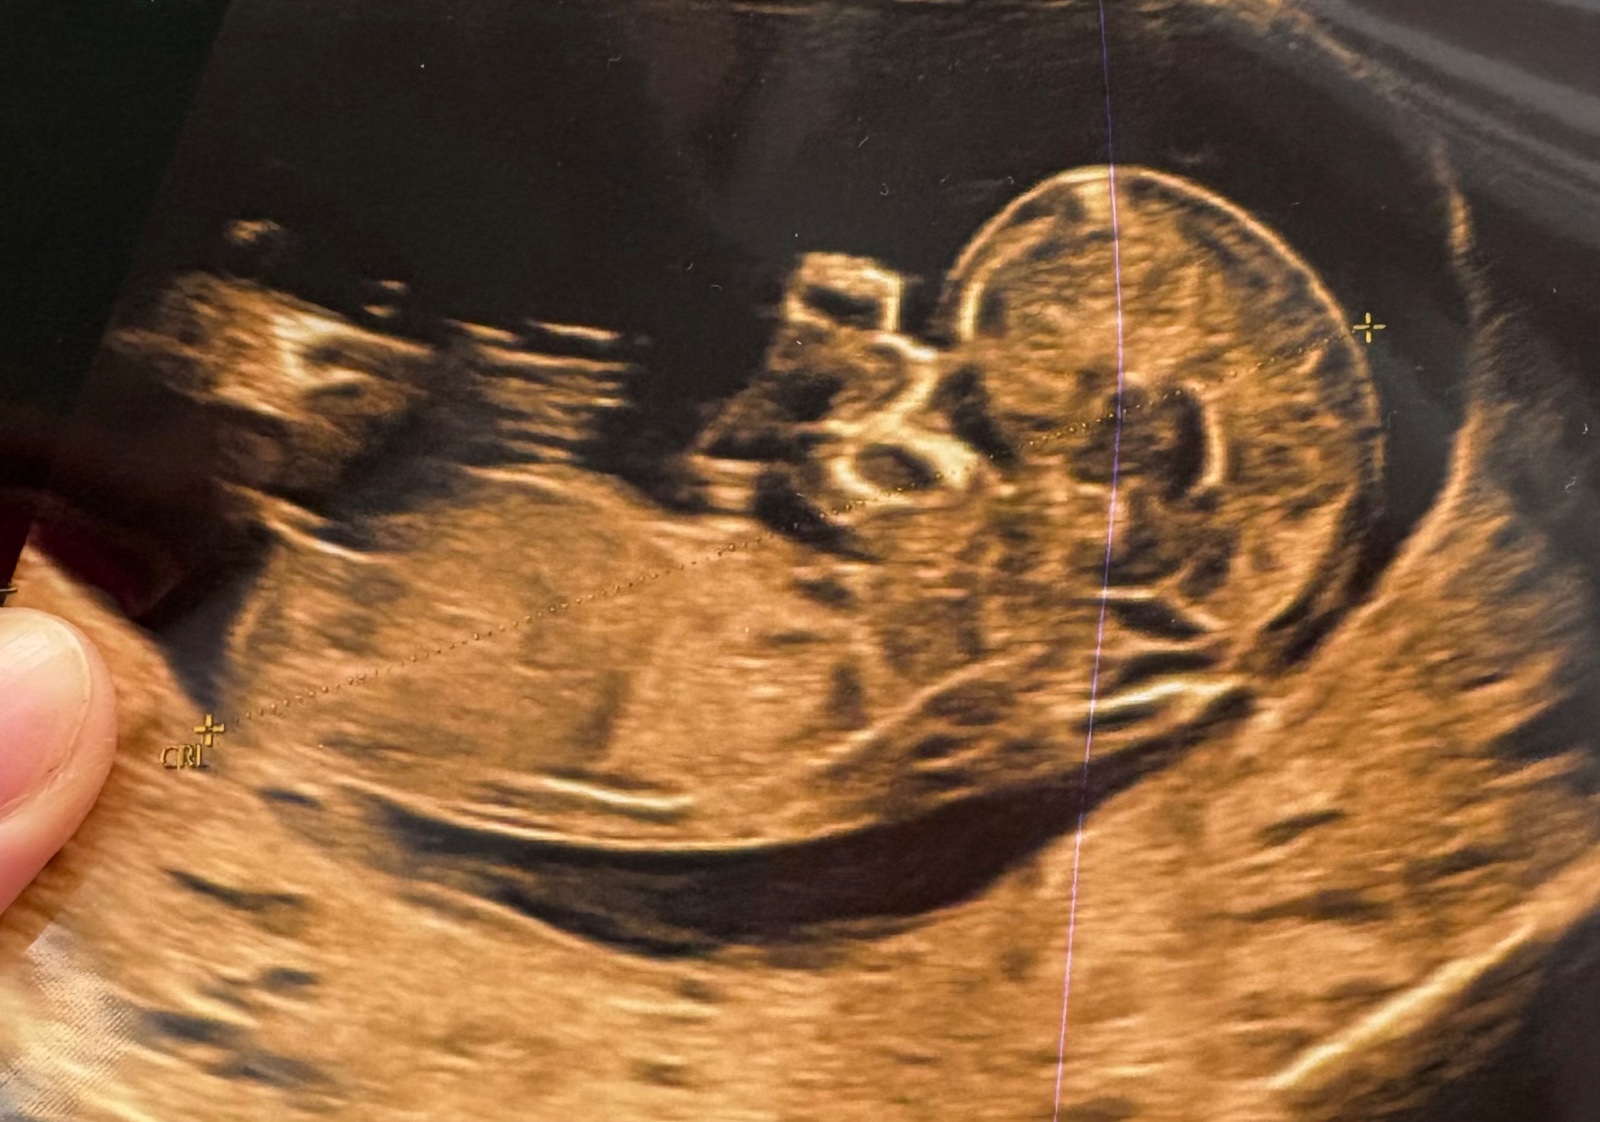

Fotka z prvního screeningu. Holčička nebo chlapeček?

ráda bych se prosím zeptala, jestli byste podle fotky dokázal říct, jestli by to mohla být holčička nebo chlapeček. Fotka je z prvního screeningu, 12. - 13. tt.